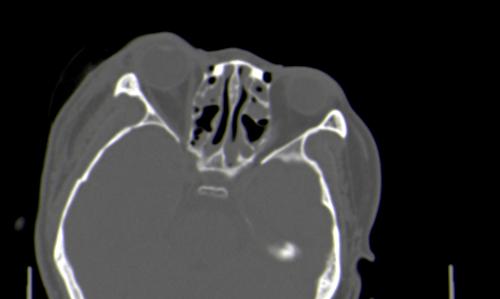

以下是引用皎皎白驹在2006-11-29 8:48:00的发言:[br]影像表现:双侧筛窦和上颌窦、鼻腔内均密度增高,右侧视神经增粗、弯曲,左筛窦顶部筛板及右侧纸板近视神经孔区可见骨折线。[br]结合临床表现考虑:右侧筛窦纸板近视神经孔区骨折致右侧视神经损伤。最好做个眼眶冠状扫描,更明确右侧视神经管是否狭窄。

以下是引用w_jianhua在2006-11-29 10:07:00的发言:[br]影像表现:双侧筛窦和上颌窦、鼻腔内均密度增高,右侧视神经增粗、弯曲,左筛窦顶部筛板及右侧纸板近视神经孔区可见骨折线。[br]结合临床表现考虑:右侧筛窦纸板近视神经孔区骨折致右侧视神经损伤。最好做个眼眶冠状扫描,更明确右侧视神经管是否狭窄。 [br] [br]支持[br]

以下是引用守望可可西里在2006-11-29 9:46:00的发言:[br][quote]以下是引用皎皎白驹在2006-11-29 8:48:00的发言:[br]影像表现:双侧筛窦和上颌窦、鼻腔内均密度增高,右侧视神经增粗、弯曲,左筛窦顶部筛板及右侧纸板近视神经孔区可见骨折线。[br]结合临床表现考虑:右侧筛窦纸板近视神经孔区骨折致右侧视神经损伤。最好做个眼眶冠状扫描,更明确右侧视神经管是否狭窄。